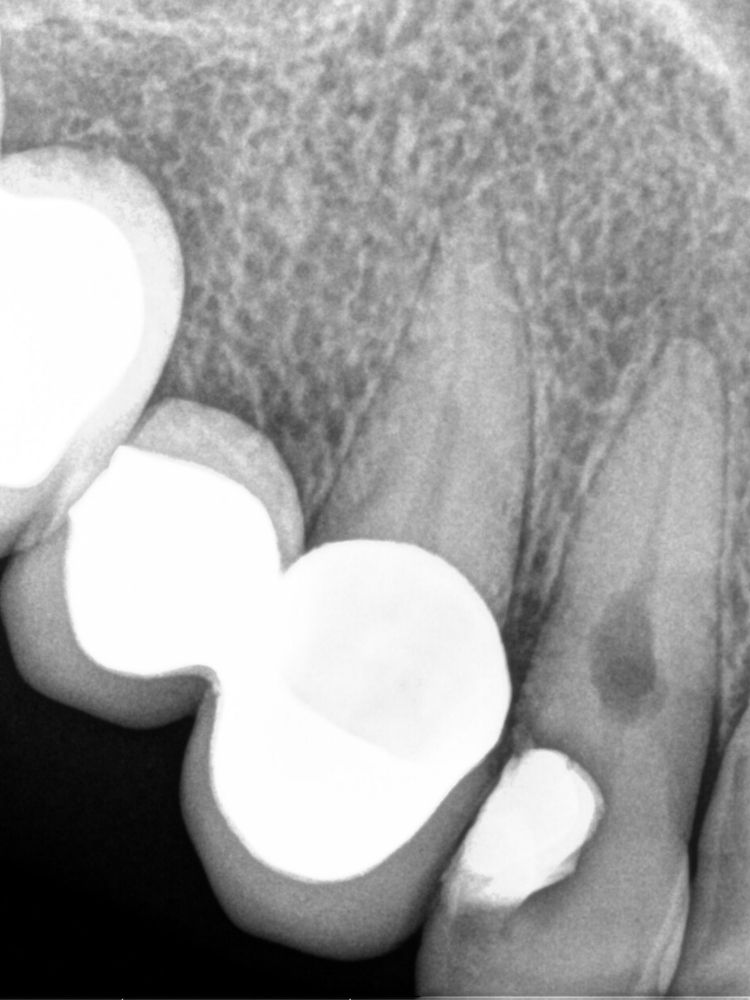

Tras esa primera consulta, al realizar la radiografía pudimos observar una imagen radiolúcida en el tercio medio del conducto. Procedimos a efectuar las pruebas diagnósticas pertinentes, de las que concluimos que el tratamiento a seguir debía ser la realización de una endodoncia o tratamiento de conducto y sellar la reabsorción interna.

En una primera visita realizamos la instrumentación del conducto y la irrigación del mismo y de la cavidad de la reabsorción. Para mejorar el tratamiento del conducto se deja en su interior un material muy específico, denominado hidróxido de calcio.